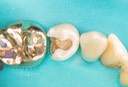

Chris Woo #3 amalgam removal – Version 2

Chris Woo #3 amalgam removal